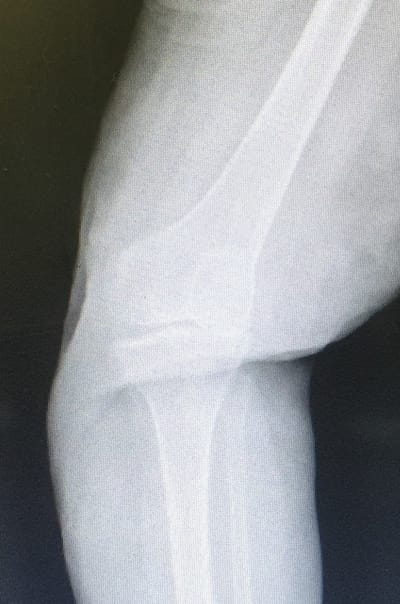

Si stima che in Italia vi siano 4 milioni di persone artrosiche. Sempre l’artrosi è la principale causa di invalidità oltre sessant’anni. L’epidemiologia ci dice che dopo 55 anni più dell’80% dei pazienti manifesta segni radiologici di artrosi: ciò vuol dire che oltre otto persone su 10, se dovessero eseguire una radiografia di un’articolazione, leggeranno nel referto” segni di artrosi”.

Essa rappresenta la degenerazione (usura) dell’articolazione che entro certi limiti va considerata fisiologica. Quando questa usura offre limitazioni funzionali, cioè impedisce lo svolgimento delle normali attività, entriamo nell’ambito patologico e quindi dobbiamo pensare ad un trattamento congruo al fine di restituire una buona qualità di vita.

Quali esami?Nella quasi totalità dei casi le radiografie sotto carico (cioè eseguite mentre il paziente è in piedi ) sono le uniche indagini necessarie.

Esse dimostrano il grado e la localizzazione dell’usura e lo stato legamentoso, consentendo quindi la scelta dell’impianto idoneo.